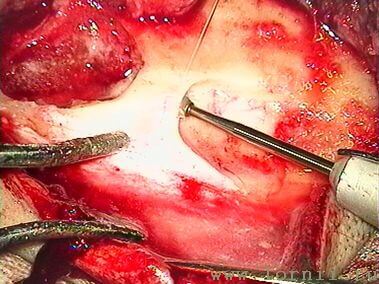

Затем борами подготавливали ложе, устанавливали и фиксировали в ложе имплант (рис. 9, 10). Соединительный кабель проводился через заднюю тимпаностому в барабанную полость.